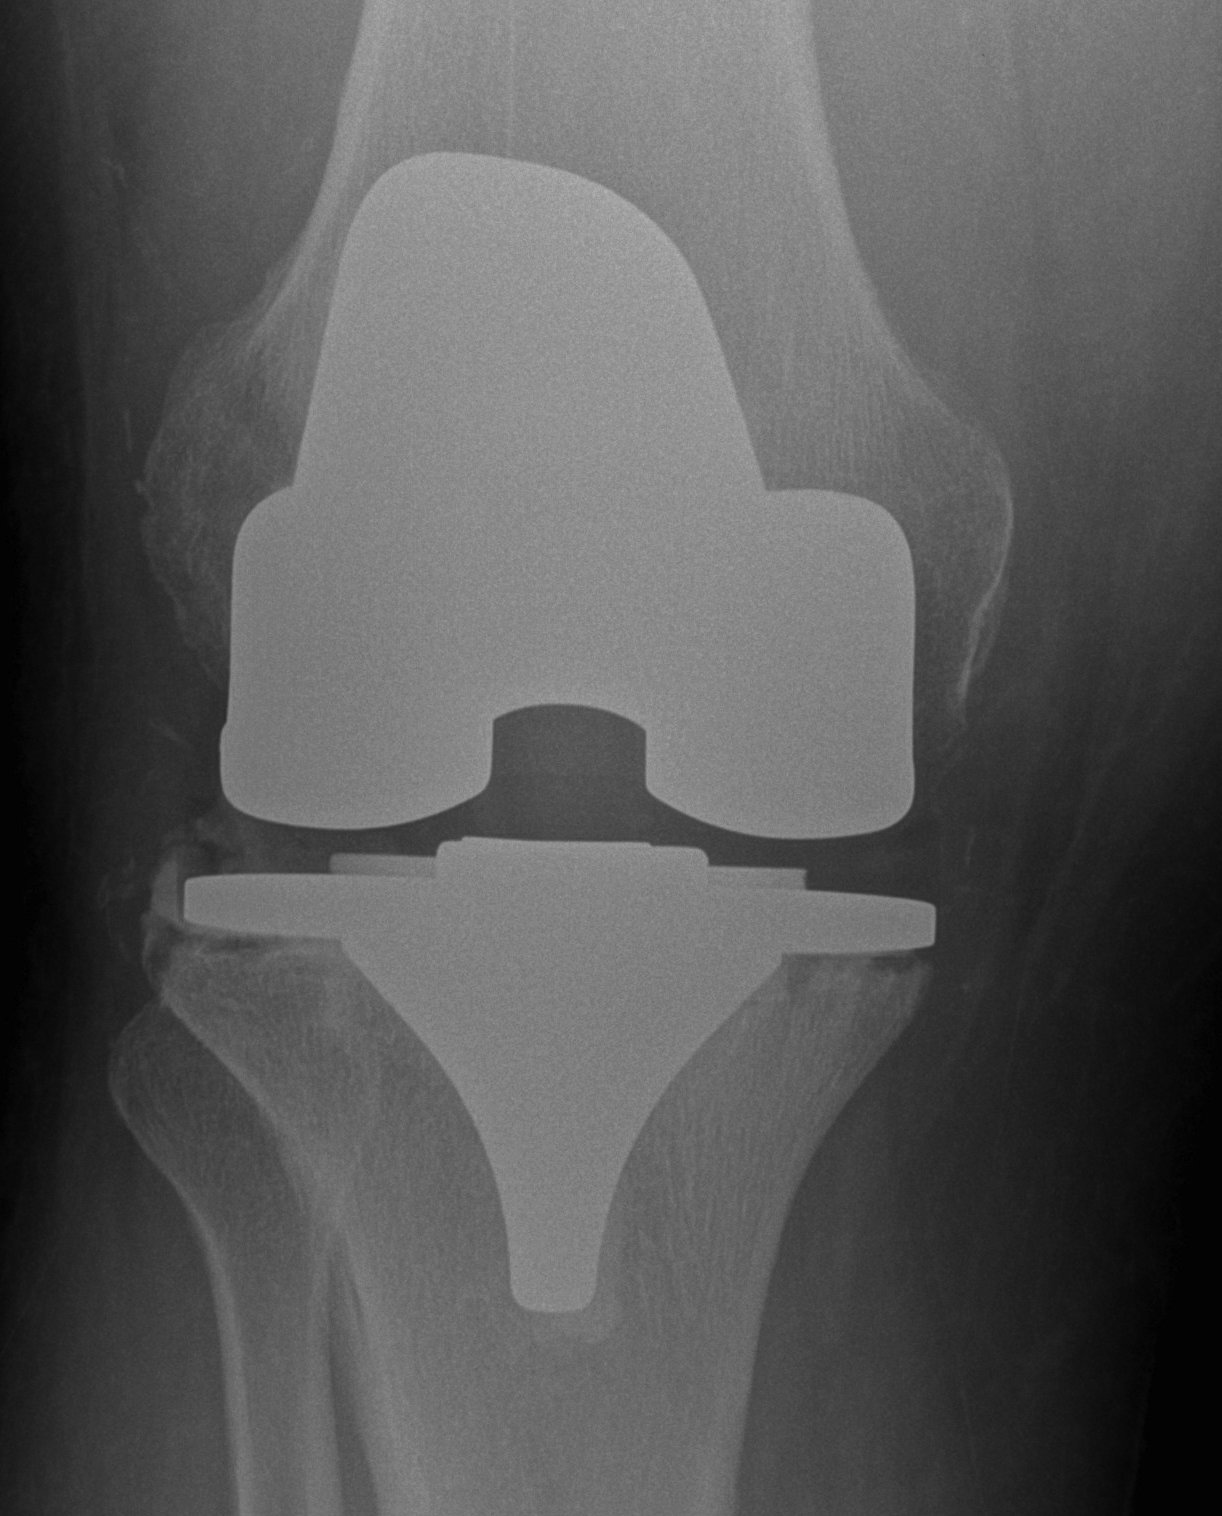

Xray

- progressive early lysis

Insertion of stemmed revision prosthesis with augments

- constraint as required

- antibiotic cement